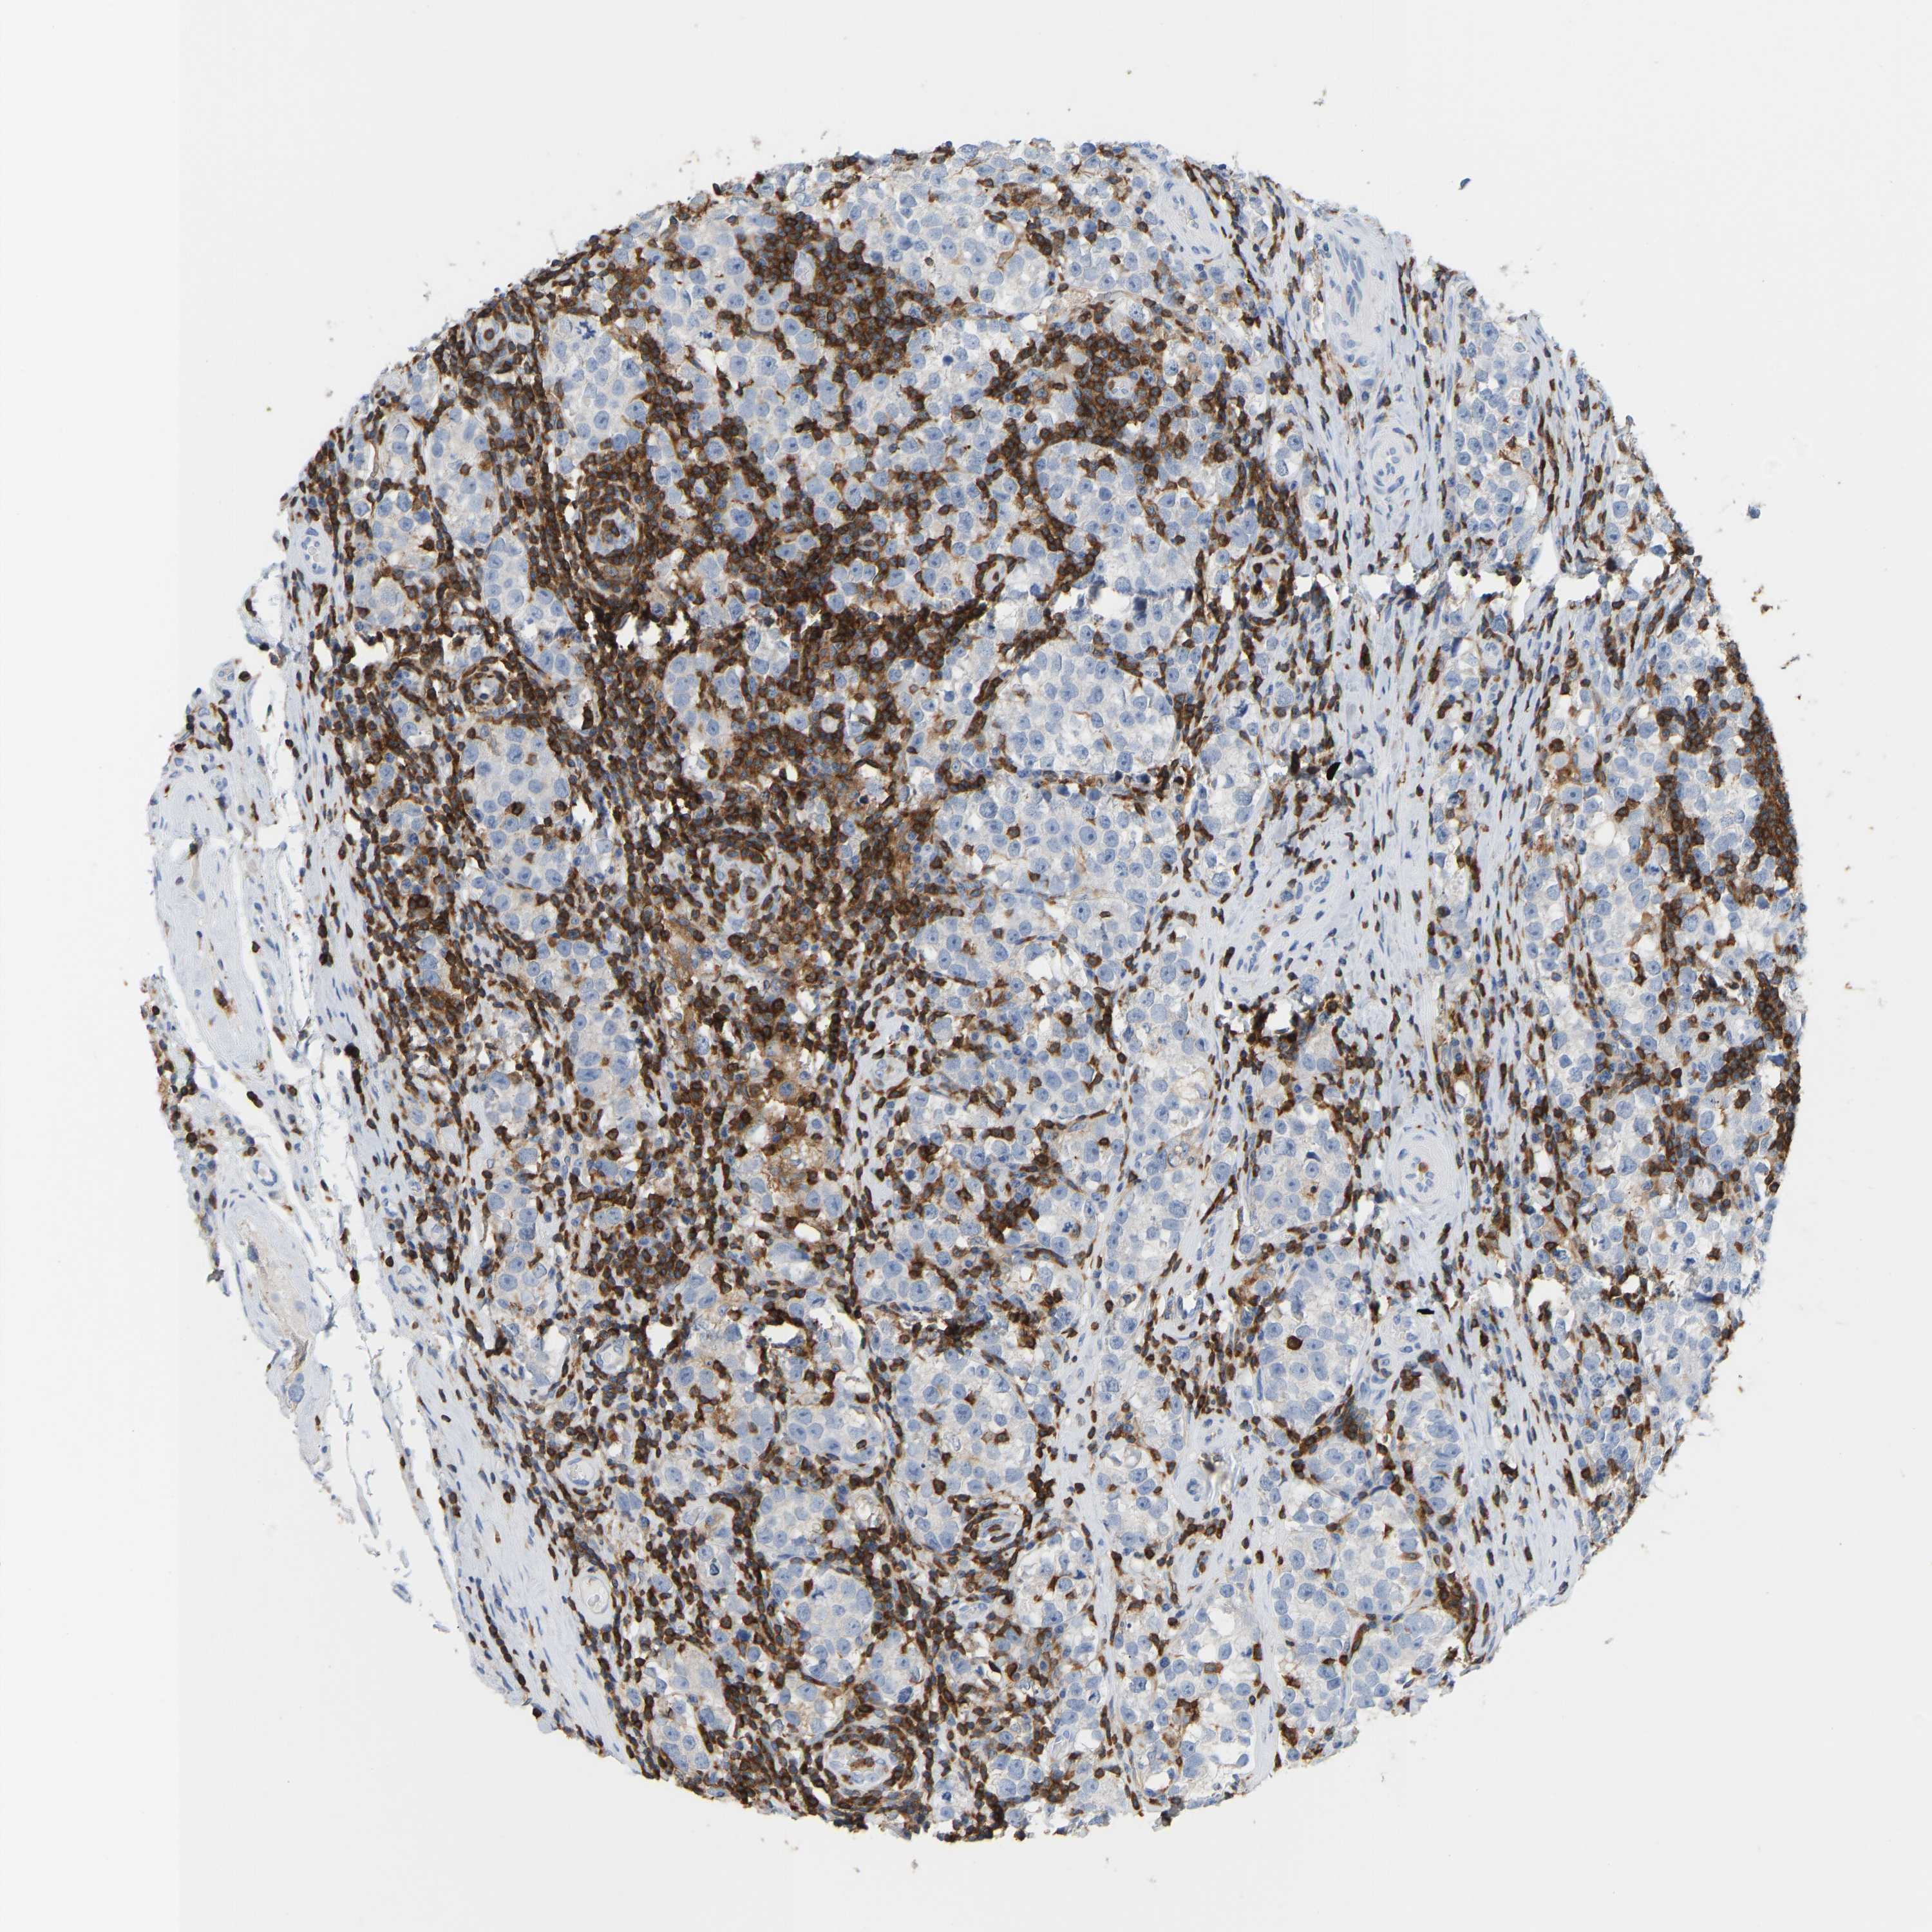

TESTIS CANCER - Protein expressioni

A mouse-over function shows sample information and annotation data. Click on an image to view it in a full screen mode. Samples can be filtered based on level of antibody staining by selecting one or several of the following categories: high, medium, low and not detected. The assay and annotation is described here.

Note that samples used for immunohistochemistry by the Human Protein Atlas do not correspond to samples in the TCGA dataset.

Antibody stainingi

Antibody staining in the annotated cell types in the current human tissue is reported as not detected, low, medium, or high, based on conventional immunohistochemistry profiling in selected tissues. This score is based on the combination of the staining intensity and fraction of stained cells.

Each image is clickable and will lead to virtual microscopy that enables deeper exploration of all samples and also displays staining intensity scores, fraction scores and subcellular localization as well as patient and tissue information for each sample.

Antibody HPA018849

Antibody CAB033987

Carcinoma, Embryonal, NOS

Seminoma, NOS